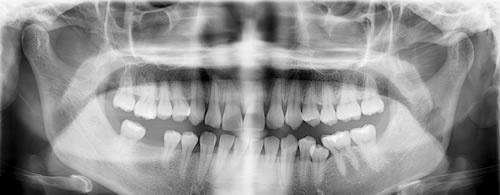

3不正常生长的智齿是什么样?

不正常生长的智齿有:横着的,斜向前的,斜向后的等等奇形怪状都有。

如下图: